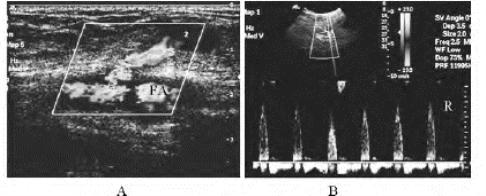

1.26.4四、动脉闭塞性疾病

1.26.5五、动脉瘤